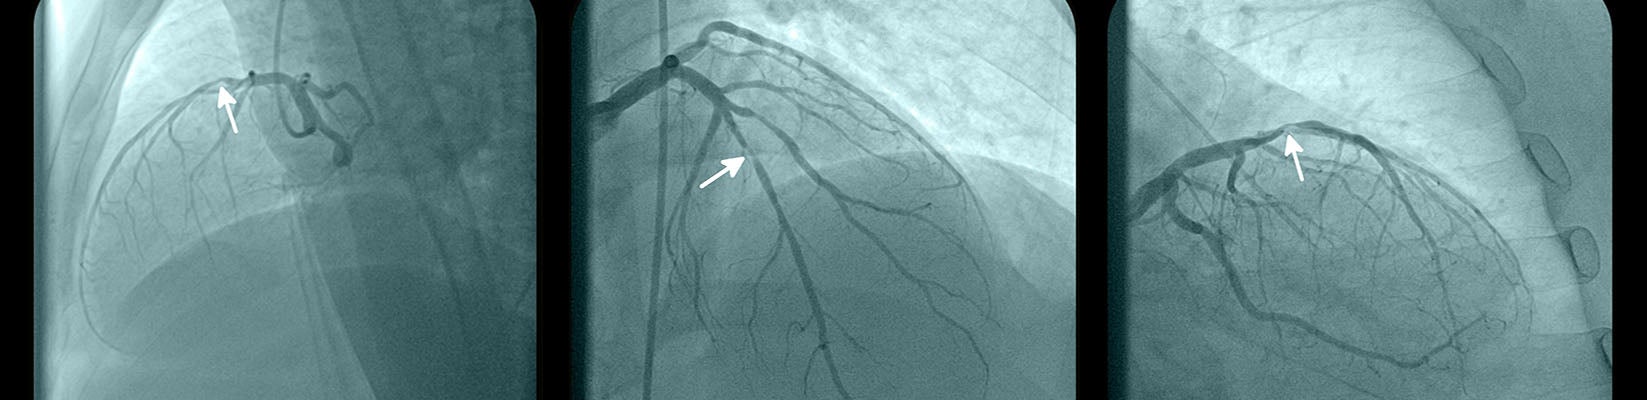

Interventional cardiology involves diagnosing and treating conditions of the heart and blood vessels using nonsurgical, catheter-based procedures and specialized imaging.

- Cardiac catheterization